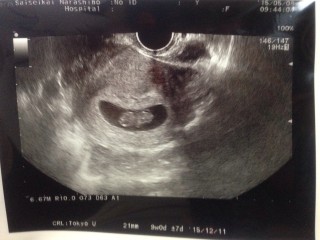

元気な心音と人間らしくなった赤ちゃん★おねんねしてたみたいで、動いてる姿は見れなかったけど手足がちゃんと生えててニヤニヤが止まらないです!CRL=25.4㎜母子手帳も無事に貰いました!

前回の検診の時から急成長で、すっかり人間らしい形に。大きさ3.2cm。手足をバタバタ動かしてすこぶる元気でした(*^^*)つわりで辛い2週間だったけど、可愛い姿を見れてまた次の検診まで頑張ろうと思えました。

赤ちゃん3.2㎝。前の検診では1週間位の誤差がありましたが、今回は計算週の大きさまで育っていました。 臍の緒?みたいなのが見てれ感動しました。念願の母子健康手帳もいただいてきました☆